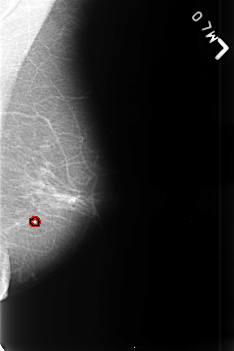

B_3447_1.LEFT_MLO

FILE: B_3447_1.LEFT_MLO.OVERLAY

TOTAL_ABNORMALITIES 1

ABNORMALITY 1

LESION_TYPE CALCIFICATION TYPE ROUND_AND_REGULAR DISTRIBUTION N/A

ASSESSMENT 2

SUBTLETY 4

PATHOLOGY BENIGN_WITHOUT_CALLBACK

TOTAL_OUTLINES 1

BOUNDARY